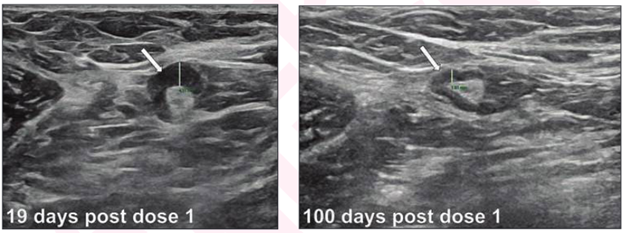

A nuanced approach is needed to weigh the risk of vaccination-associated axillary lymphadenopathy against the risk of delaying breast cancer screening.